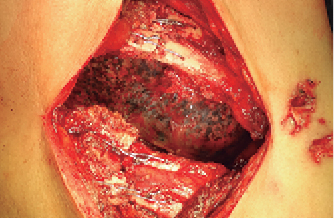

Se presenta el caso de un paciente de 72 años de edad con historia de haber sufrido caída de un árbol 21 días antes. Fue atendido en un hospital departamental donde le realizaron radiografía de tórax (Figura 1), que mostraba fracturas simples de varios arcos costales del hemitórax derecho con hundimiento de la parrilla costal. La TAC de tórax (Figura 2) muestra fracturas del 3o al 9o arcos costales derechos, con borramiento del ángulo costodiafragmático y colapso pulmonar basal del mismo lado.